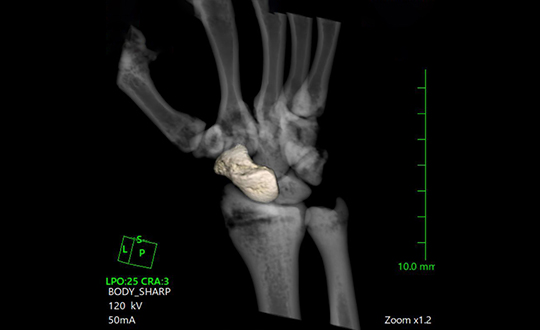

高速・高精細撮影により短時間で体内を詳しく撮影できるCT装置。80列検出器による高速撮影とAIDR 3D Enhanced技術で被ばくを低減し、安全性と精度の高い検査を行います。

デジタル技術により高画質と低被ばくを両立したレントゲン装置。ISS方式の自動撮影条件設定や長尺撮影に対応し、全脊椎・全下肢の一括撮影も可能。短時間で体への負担が少ない検査を行います。

関節疾患、スポーツ障害、骨折など、幅広い症例に対応可能で、患者様一人ひとりに合わせた治療方針を提案しています。術前検査から術後フォローまで一貫した対応が可能であり、地域の先生方との連携のもと、必要な症例に対し迅速かつ的確に対応します。